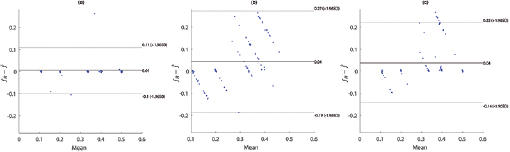

Standard image High-resolution imageFigure 5. Bland–Altman plots for fPPG (a), CvPDR (b), and CvPDR+TR (c).

Download figure:

Bland–Altman plots show a positive bias in all considered methods, indicating an underestimation of the respiratory rate. However, a detailed analysis of figure 5 indicates an overestimation at low respiratory rates. Additionally, fPPG presents a lower standard deviation (SD) than vPPG-based methods, and the inclusion of the tracking signal reduces the SD of the error.